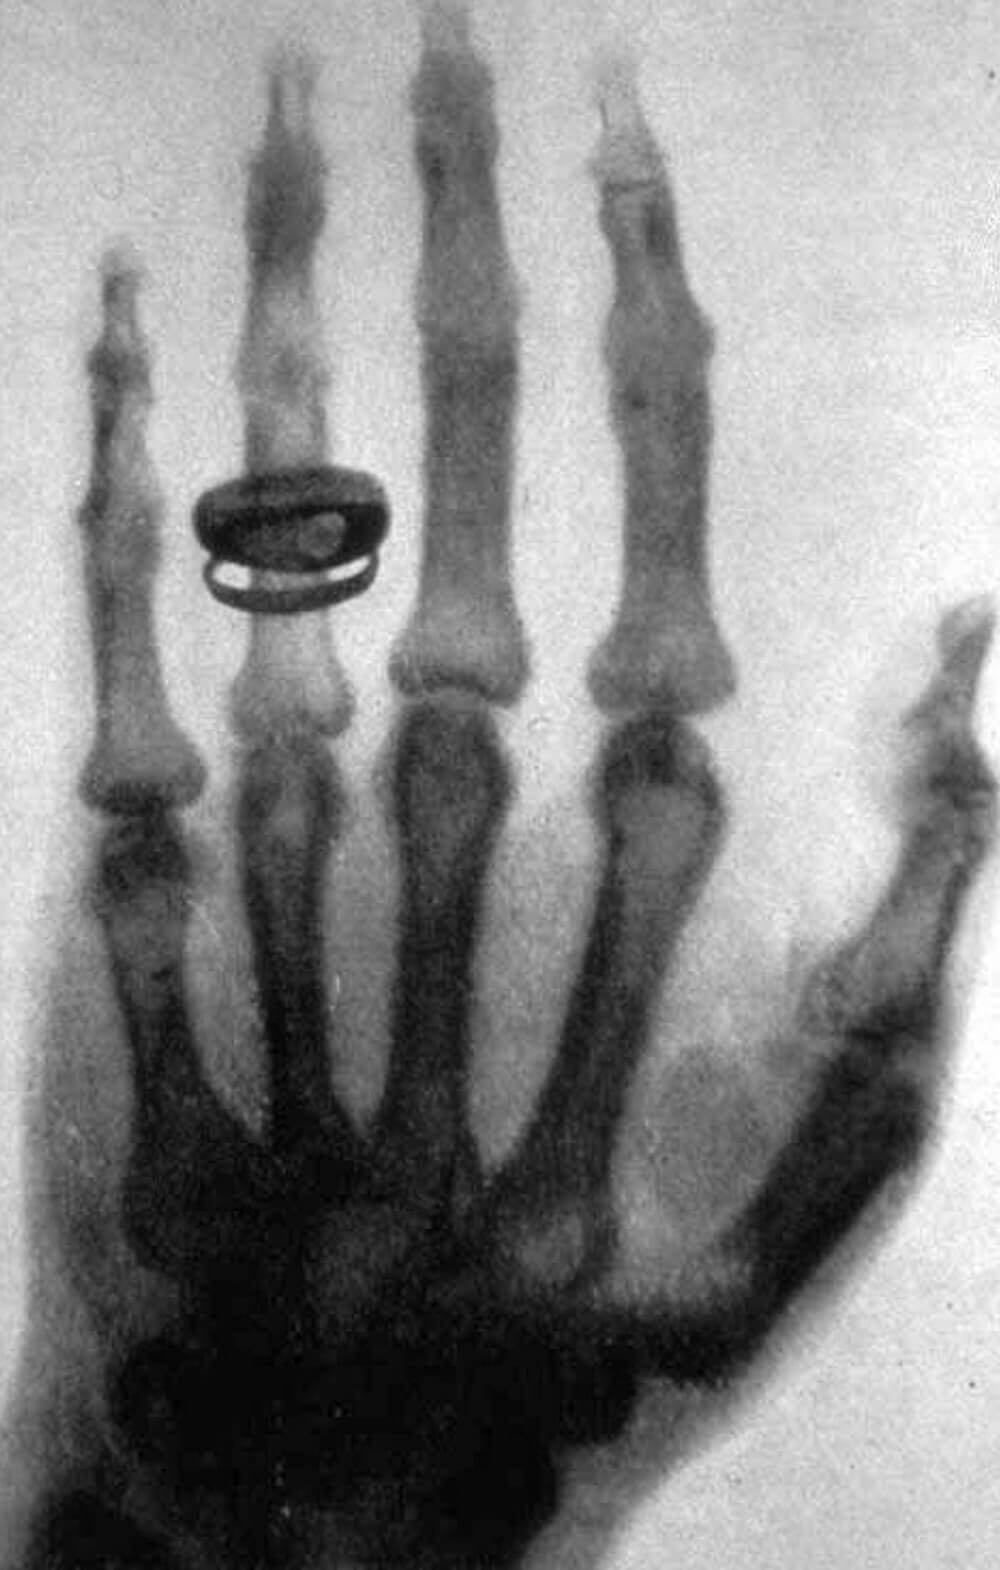

Wilhelm Conrad Röntgen (1845 – 1923) war ein deutscher Physiker, der 1868 sein Studium als Maschineningenieur an der ETH Zürich abschloss. Im Jahre 1895 entdeckte er die nach ihm benannten Röntgenstrahlen. Seine Apparatur hatte die Strahlen erzeugt, zuerst noch unbemerkt, da für den Menschen nicht sichtbar. Er fand dann aber heraus, dass seine Fotoplatten offenbar durch eine unsichtbare Strahlung belichtet worden waren.

Image, public domain

Heutzutage sind Röntgenstrahlen nicht mehr wegzudenken. Sie haben eine ausserordentliche Bedeutung in der Medizin, aber auch in der Astronomie, Materialforschung und -analyse. Auch in der Biochemie werden Röntgenstrahlen für die Kristallographie von Proteinen eingesetzt.